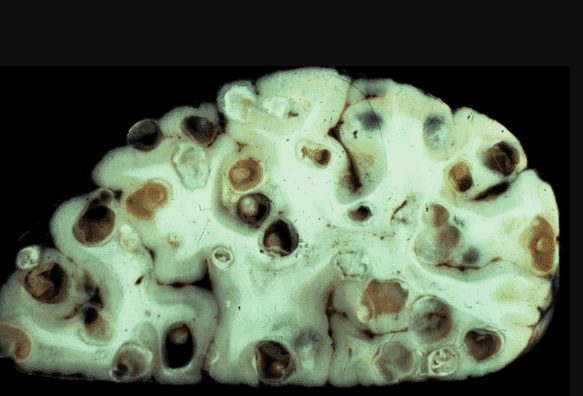

Мозок, уражений паразитами

Інший випадок: чоловік, 61 рік. Помер від цирозу печінки. Родичі думають, що винен алкоголь. Тільки випивав він не так багато, і слідів алкогольного руйнування печінки немає, натомість печінка була просто поїдена паразитами, я виявив сотні ходів, якими хробаки переміщалися.

Ще одна недавня історія. Пацієнтка померла від раку кишківника, спричиненого паразитами. Паразити отруюють здорові клітини своїми токсинами, через що вони змушені перероджуватися, змінювати свою структуру. І перероджуються вони саме в ракові клітини, які агресивніші й здатні протистояти паразитам. Але для людини ці клітини згубні. Пухлина швидко розвивається і пускає метастази. Людина гине протягом лічених місяців.

На фото нижче можете побачити знімок кишечника. Пацієнтка померла від раку кишківника, спричиненого паразитами. Паразити отруюють здорові клітини своїми токсинами, через що вони змушені перероджуватися, змінювати свою структуру. І перероджуються вони саме в ракові клітини, які агресивніші й здатні протистояти паразитам. Але для людини ці клітини згубні. Пухлина швидко розвивається і метастазує. Людина гине протягом лічених місяців.